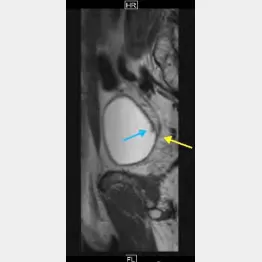

12月27日に東大病院に入院し、翌日に手術を受けました。下半身麻酔でしたから、電気メスによる切除の様子もモニター画面で見ることができました。40分という短時間で完全に取りきれたのは幸いです。しかし、再発予防で膀胱内に抗がん剤注入も受けています。